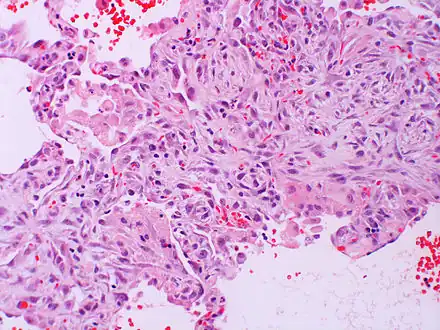

Micrograph of diffuse alveolar damage, the histologic correlate of acute interstitial pneumonitis. H&E stain.

Rapid progression from initial symptoms to respiratory failure is a key feature. An X-ray that shows ARDS is necessary for diagnosis (fluid in the small air sacs (alveoli) in both lungs). In addition, a biopsy of the lung that shows organizing diffuse alveolar damage is required for diagnosis. This type of alveolar damage can be attributed to nonconcentrated and nonlocalized alveoli damage, marked alveolar septal edema with inflammatory cell infiltration, fibroblast proliferation, occasional hyaline membranes, and thickening of the alveolar walls. The septa are lined with atypical, hyperplastic type II pneumocytes, thus leading to the collapse of airspaces. Other diagnostic tests are useful in excluding other similar conditions, but history, X-ray, and biopsy are essential. These other tests may include basic blood work, blood cultures, and bronchoalveolar lavage. The clinical picture is similar to ARDS, but AIP differs from ARDS in that the cause for AIP is not known.